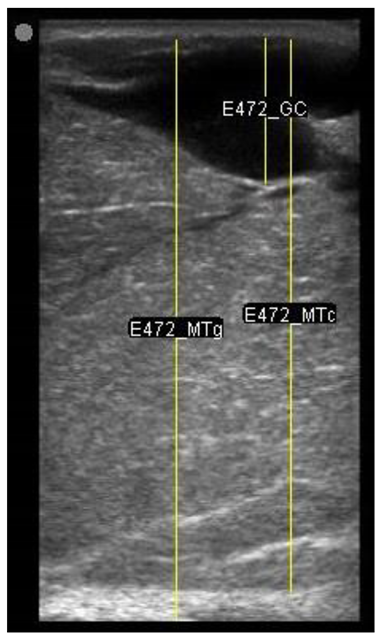

| 109 days of pregnancy (P109) Scanning depth 4.7 cm | ![]() | ![]() | MT generous: 36.8 mm MT conservative: 27.2 mm Gland cistern: 4.7 mm Parenchyma: 15.4 mm Fat Pad: 5.5 mm |